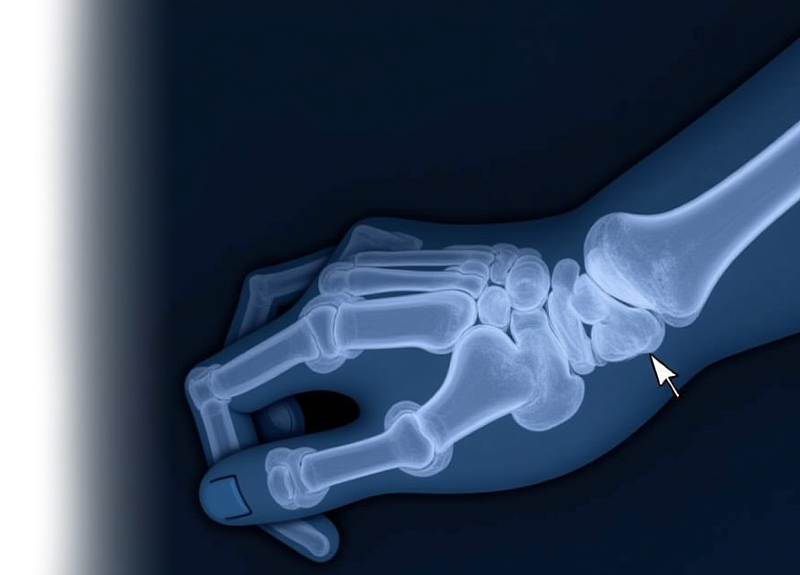

Компьютерная томография кисти – важный метод прицельного исследования состояния кисти.

Это неинвазивное обследование, которое позволяет специалистам провести диагностику различных заболеваний и травм кисти.

КТ позволяет исключить патологию кисти костно-травматологического, дегенеративного генеза, изменений, характерных для системного заболевания.